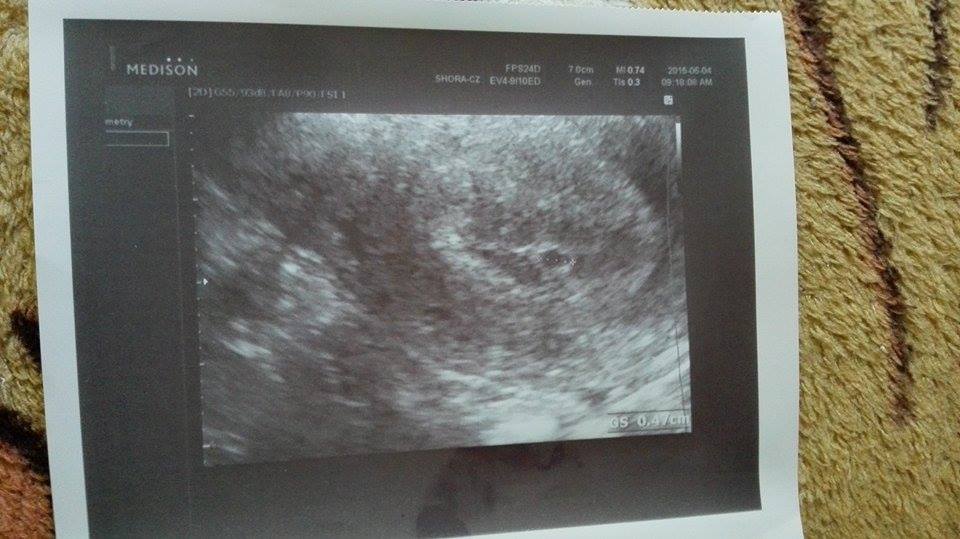

@sukynecka01 tak to jsem na tom stejně, já poslední ms 30.4., 1.6. mi ultrazvuk ukázal to co tobě 🙂

@sukynecka01 tak to jsi dle PM 5+2.... 🙂

@te_reza no mě 1.6 nic až včera tu foto a ty si kolik tak cca? já mám jít zase za týden mi řekne víc

@sukynecka01 No nejdřív mě ujišťovala, že můžu mít test falešně pozitivní a pak byla sama překvapená, že tam něco je... prý to je tak 2-3 týdny a na kontrolu jdu 17.6. to mi řekne víc. Toho 1.6. mi pouze řekla, že jsem na začátku těho

@te_reza no já jdu 11.6 no uvidím co řekne podle ms to , tak vypadá že sme 4-5 týdnů říkala ti hladinu hcg nebo brala ti krev

@sukynecka01 Ne, nic, jen že to je zárodek plodu a ať příjdu za 2-3 týdny, že mi řekne víc, tak jdu 17.6., snad stihne povyrůst 🙂